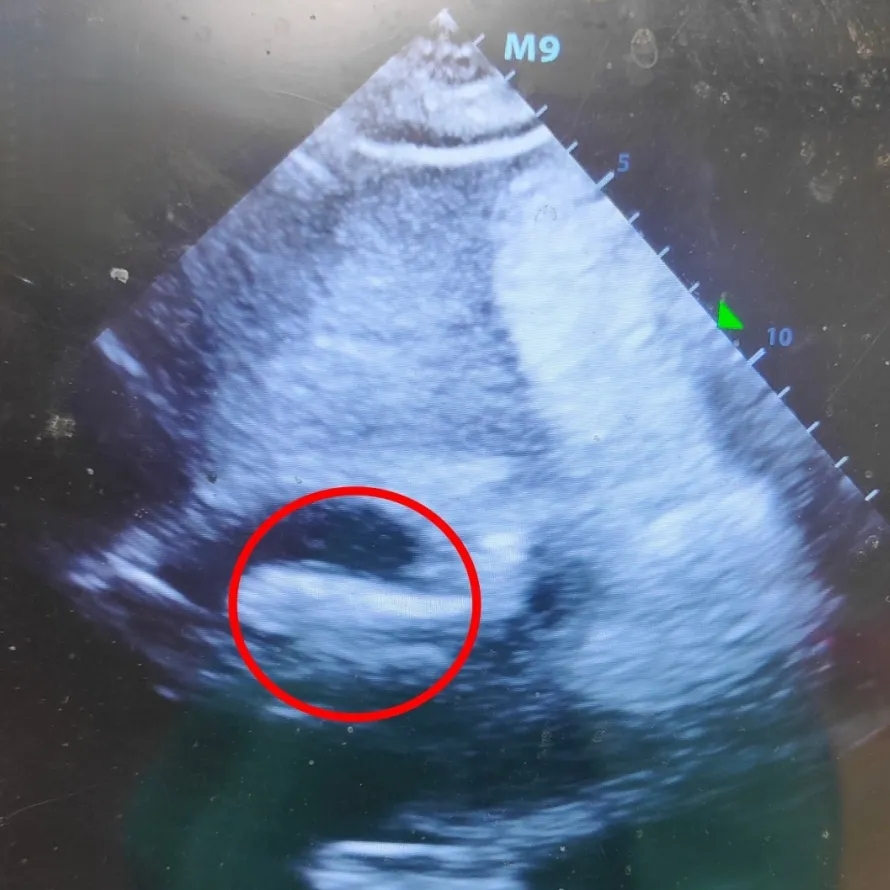

食道超声下可见房间隔膨出瘤摆动幅度较大

经食道超声(TEE):原发隔与继发隔回声分离,二者重叠长度约10mm,分离高度左房侧3.2mm,右房侧5.2mm。房间隔伸展径38mm,薄软段长,前后径约29mm、上下径约23mm,明显左右摆动,摆动幅度>15mm。房间隔原发隔与继发隔间探及斜行低速双向分流。左心耳排空速度约61cm/s。二、三尖瓣少量反流。